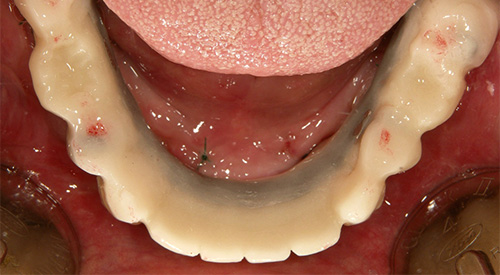

インプラント埋入直後

インプラント埋入当日の仮歯